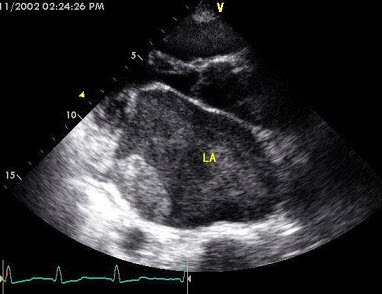

61、单项选择题

图为小儿超声心动图,根据此切面可以看到哪些腔室结构()

A.左房、左室、主动脉、右室、右房

B.左房、左室、主动脉、右室、右室流出道

C.左房、左室、主动脉、右室

D.左房、左室、右室、右房

E.左房、左室、主动脉、左心耳、右室、右房、右室流出道